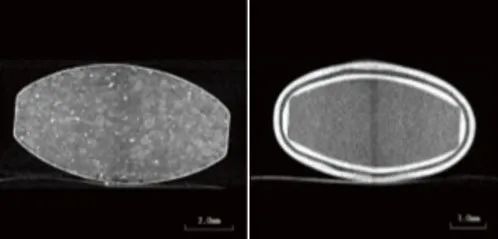

在本例中,觀察到兩種具有不同結構的片劑(片劑A和B)(圖2)。片劑的透視圖像如圖3所示。

圖4片劑A的CT效果圖(左)圖5片劑B的CT效果圖(右)

分析片劑圖像的一個例子除了觀察片劑內部外,CT X射線圖像還可用于執(zhí)行各種圖像分析。在本例中,利用CT數(shù)據(jù)結合三維圖像處理軟件,分析藥物的分布狀態(tài),分析藥物的層厚。